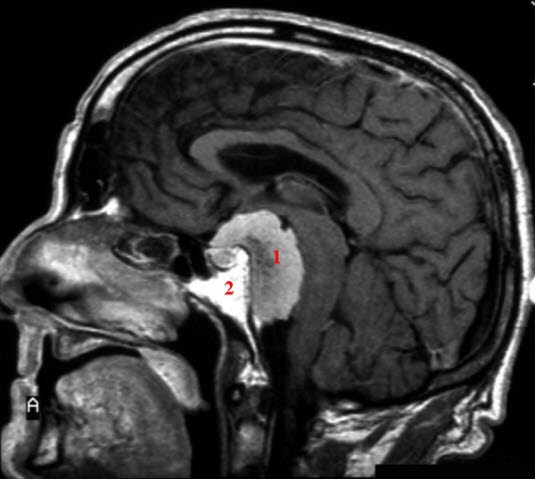

Meningiom (med kontrast)

MR med kontrast - saggitalsnitt

1. Ødem

2. Meningeomet